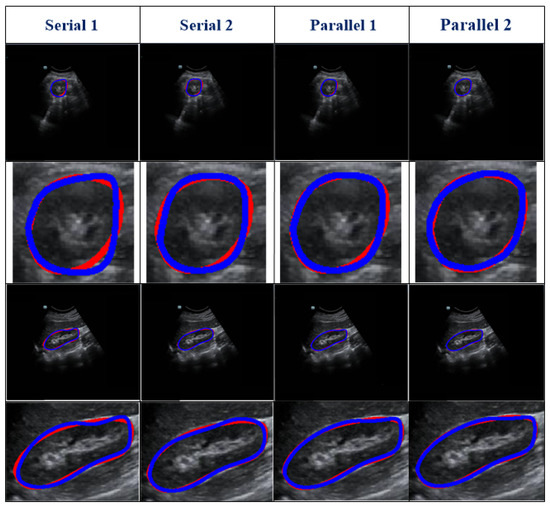

Ablation experiments were conducted to assess the influence of different components of our method. The ablation results are shown in Table 3. Figure 6 reports the visual comparisons using two representative cases. Compared with Model 1, the DSC and Ω of other models (with the refinement step) increased by 1.55–5.22% and 8.11–14.8%, respectively. In addition, for Models 2–6, the DSC values were higher than 91% and the standard deviations were lower than 6.5%. This demonstrates that the proposed refinement step can fine-tune the coarse segmentation outcomes. All in all, our model shows optimal capability.

3.3. Robustness Evaluation of Our Proposed Method Using a Testing Set Corrupted by Gaussian Noise

We used testing images corrupted by various degrees of Gaussian noise to evaluate the performance of our proposed method. Different degrees of Gaussian noise can have dissimilar influences on the capability of a method [25]. In our experiment, the standard deviation (σ) was assigned a set value (i.e., 0, 10, 25, or 50). As shown in Table 4, compared with the case in which σ = 0, when σ rose from 10 to 25, to 50, the DSC value increased from 0.96% to 1.93% and to 3.61%, respectively, and the Ω decreased from 1.85% to 2.52% and to 3.77%, respectively. However, the mean DSC values for all cases with different levels of noise were greater than 91%. The qualitative results of a randomly picked case are displayed in Figure 7.

As shown in Figure 6, we used an ablation comparison to demonstrate the capability of our method. The regions indicated by arrows are missing or ambiguous due to different factors. The white and green arrows indicate the blurry boundary of the kidney caused by intestinal gas and the spleen, respectively. The orange arrow indicates the ambiguous boundary of the kidney due to the kidney’s thickness and internal structure (i.e., renal pelvis, calyces, blood vessels, and adipose tissue). However, the model with a refinement step still obtained highly accurate results.

As US images are grayscale, most of the pixels are black and have a gray value of zero. To better distinguish the effect of other pixel points (gray value > 0), we only selected the number of pixels within the range [0, 10,000] in the image to show the distribution of pixel points with different gray values (Table 4 and Figure 7). When we added more Gaussian noise (σ increases), the number of pixels with gray values greater than 0 increased. This illustrates that the degree of damage to the original images increased. However, the DSC values were greater than 90% even for images with a severe level of noise (σ = 50). This indicates that the blurry boundaries were efficiently detected (Table 3 and Figure 7). Figure 8 shows zoomed-in images corresponding to those in Figure 7.

Figure 6. Discussion of the impact of each module of our proposed method. The arrows show missing or blurry boundaries. The blue and red curves represent the experimental outcome and GT, respectively.

Figure 7. Robustness of our method under various degrees of Gaussian noise. Row 1, raw or noisy data; row 2, histograms of the raw or noisy images; row 3, the overlap between the GT and segmentation results; and row 4, corresponding zoomed-in results. The red line represents the GT, and the blue line represents the segmentation result.